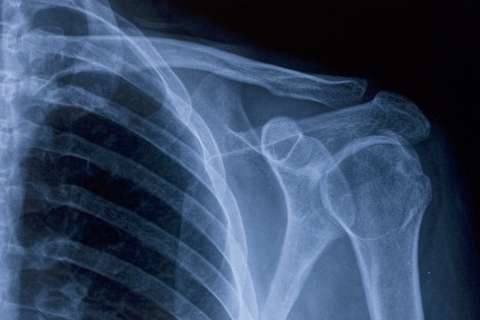

Our team includes orthopedic experts specializing in areas such as spine care, joint replacement, hand surgery and pediatric care. Many people get better with nonsurgical treatments, such as physical therapy or injections. If you do need surgery, you're in expert hands.